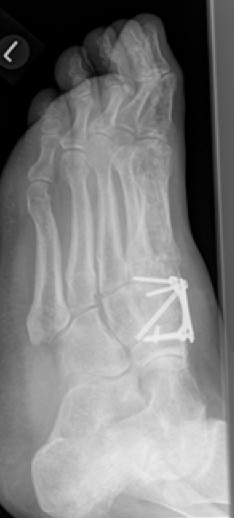

2.-Postoperatives Bild Februar 2017

Die indizierte Operation wurde im Februar 2017 durchgeführt. Die Stabilisierung der Arthrodese erfolgte mit insgesamt 3 Schrauben und Anlagerung vom Knochenersatzmaterial.